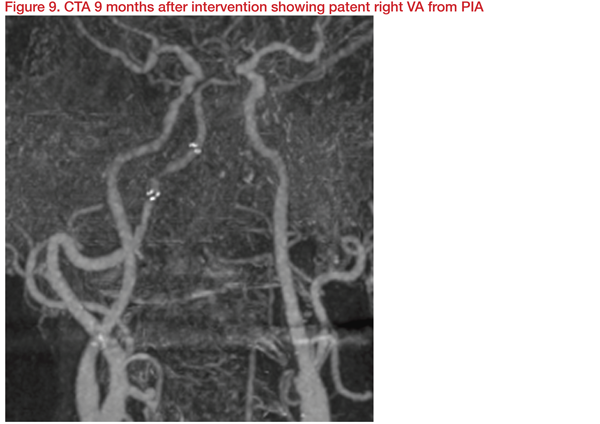

Angioplasty and stenting were carried out with Gateway 3*15mm and Wingspan 4*20mm. This achieved dilatation of right VA (PIA) from 1.2 mm to 2.4 mm and restoration of basilar flow. At discharge, clinical muscle power improved, and 10 months later, NIHSS and mRS improved to 13 and 3, respectively.